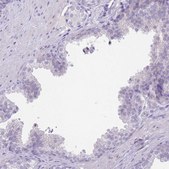

immunohistochemistry: 1:200- 1:500

- IHC tissue array of 44 normal human tissues and 20 of the most common cancer type tissues.